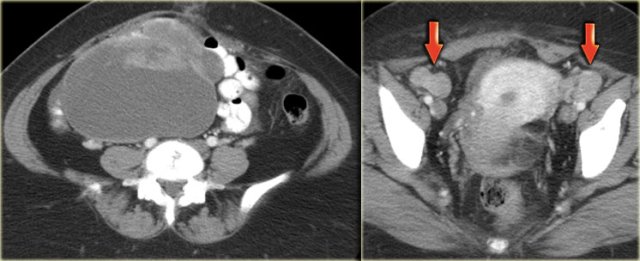

Ultrasound shows a complex solid-cystic mass in the left ovary, and another, very large complex solid-cystic mass in the right hemi-pelvis.

CT of the same patient shows a complex solid-cystic mass with thick, enhancing septations in the right ovary.

These findings are very suspicious for a malignant cystic neoplams.

There is also bilateral lymphadenopathy (arrows).

Pathology showed a serous ovarian cystadenocarcinoma.

This is the most common type of ovarian cancer.